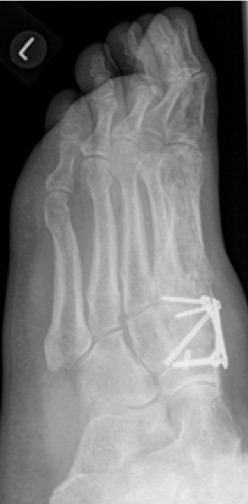

4.- 06/2017 nach Rearthrodese

Die Stabilisierung erfolgte nunmehr mittels Platte und einer externen Zugschraube. Es wurde wiederum Knochenersatzmaterial angelagert.

Bei einer Verlaufskontrolle im Juli 2017 ergab sich bei der Röntgenuntersuchung eine Fehllage einer Plattenschraube, die damit das TMT 2 überbrückte.

5.- 07/2017 Schraubenfehllage : Schraube erreicht Basis MT2 und überbrückt TMT 2